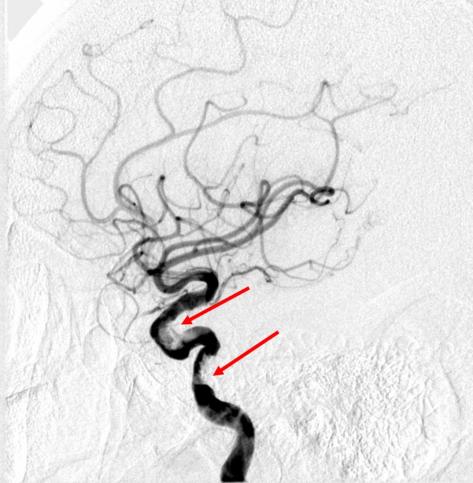

老冯(化名)因近半年间断发作视物模糊、伴间断肢体力弱,来到北大医院神经内科就诊。在门诊做了核磁检查后发现,有新近腔梗和陈旧梗死伴出血的可能,溶栓多模态CTA则提示头颈动脉粥样硬化,不除外血栓形成。为了进一步检查,老冯办理了住院,进行了脑血管造影,检查结果发现左侧颈内动脉存在充盈缺损,高度怀疑为血栓性病变。

脑血管造影,箭头所示为狭窄部位,考虑与血栓相关